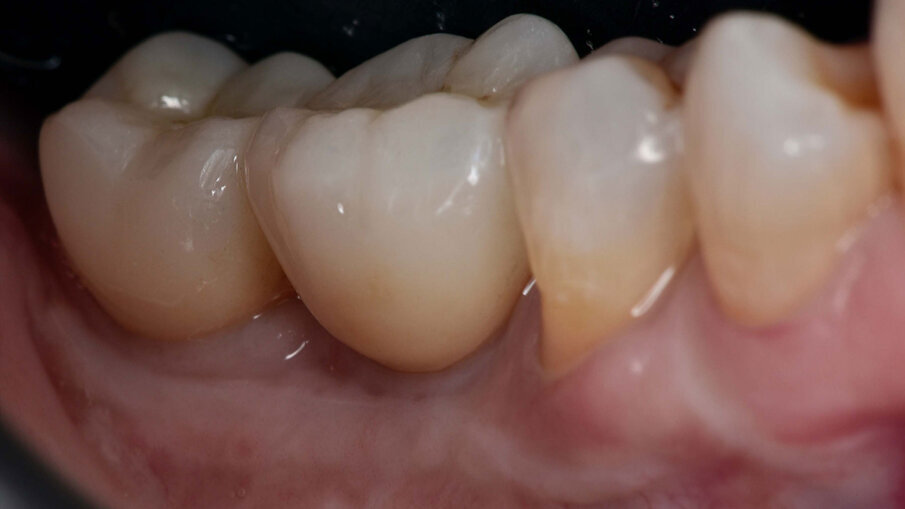

Dopo due settimane, è stata eseguita una scansione 3D con scan body e sono state consegnate due corone provvisorie avvitate sugli impianti, in modo da poter condizionare i tessuti molli peri-implantari (Figg. 11-12b). A causa di un’inadeguata banda di mucosa cheratinizzata sul versante vestibolare, è stato eseguito un intervento di vestiboloplastica con affondamento di fornice e innesto epitelio-connettivale prelevato dal palato (Figg. 13, 14). Dopo un’ulteriore maturazione dei tessuti, una nuova scansione ha permesso di dare informazioni all’odontotecnico circa il tragitto transmucoso ottenuto con i provvisori e sono state consegnate due corone definitive avvitate in zirconio (odt. Alessandro Giacometti; Figg. 15-19b). La paziente è stata seguita con controlli periodici clinici e radiografici a 6 mesi, 1 anno e 2 anni dal carico protesico (Figg. 20a, 20b).

Figg. 19a, 19b_Immagine clinica e radiografica che mostrano il manufatto protesico finale.